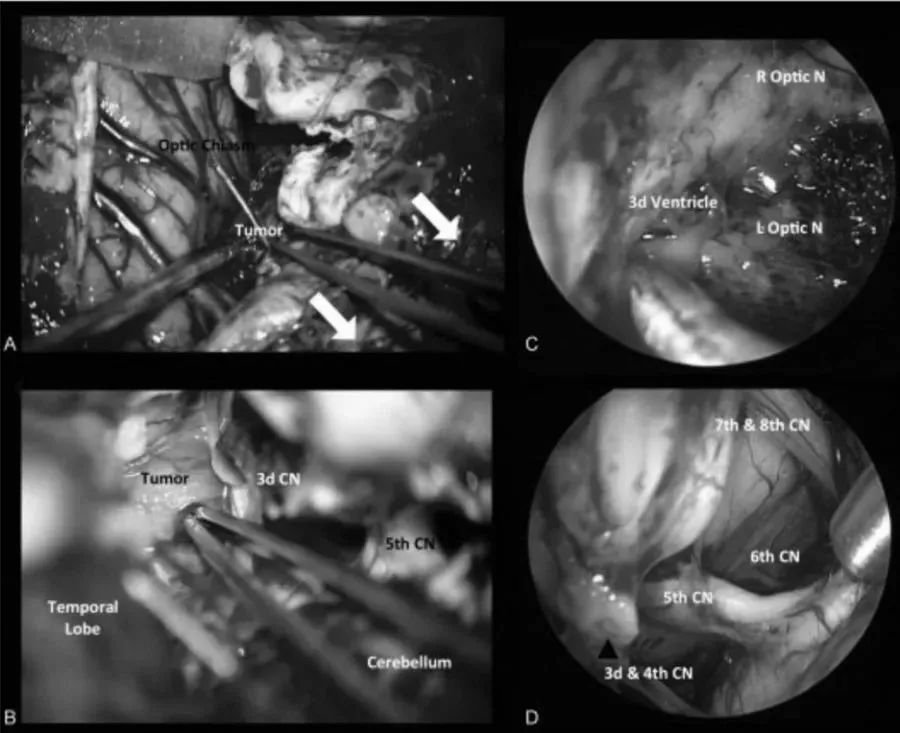

一阶段,通过经神经内镜经鼻入路进行视交叉和神经减压,从而为后续治疗做准备。然而随着肿瘤的加速生长,新的视觉缺陷出现和对下丘脑和三脑室的压迫影响,需要再次手术切除。二阶段,经后岩骨入路(或称后迷路经天幕入路)可以很好地暴露肿瘤和周围解剖结构(三脑室的底部和壁,分支血管,视神经等)。

图1后视交叉性较大颅咽管瘤患者肿瘤术前(A,C)和术后(B,D)矢状位增强MR对比,显示肿瘤全切。

图2术中图像:(A)在经后岩骨入路时,横窦-乙状窦连接处的后部移位,为颞叶与后颅窝之间的手术通道(白色箭头)。(B)脚间池蛛网膜的初步解剖分离,肿瘤的暴露。内窥镜辅助可以对手术床进行详细检查(C),以便更好地了解周围的神经血管解剖结构(D)。CN,颅神经;L视神经N,左视神经;R视神经N,右视神经。

术后情况:术后威尔视力、视野恢复正常,没有颅神经麻痹症状,认知功能好转,垂体功能恢复正常。术后配合辅助放射治疗,术前症状得到很大好转,可以如常工作,生活质量得到很大改观。